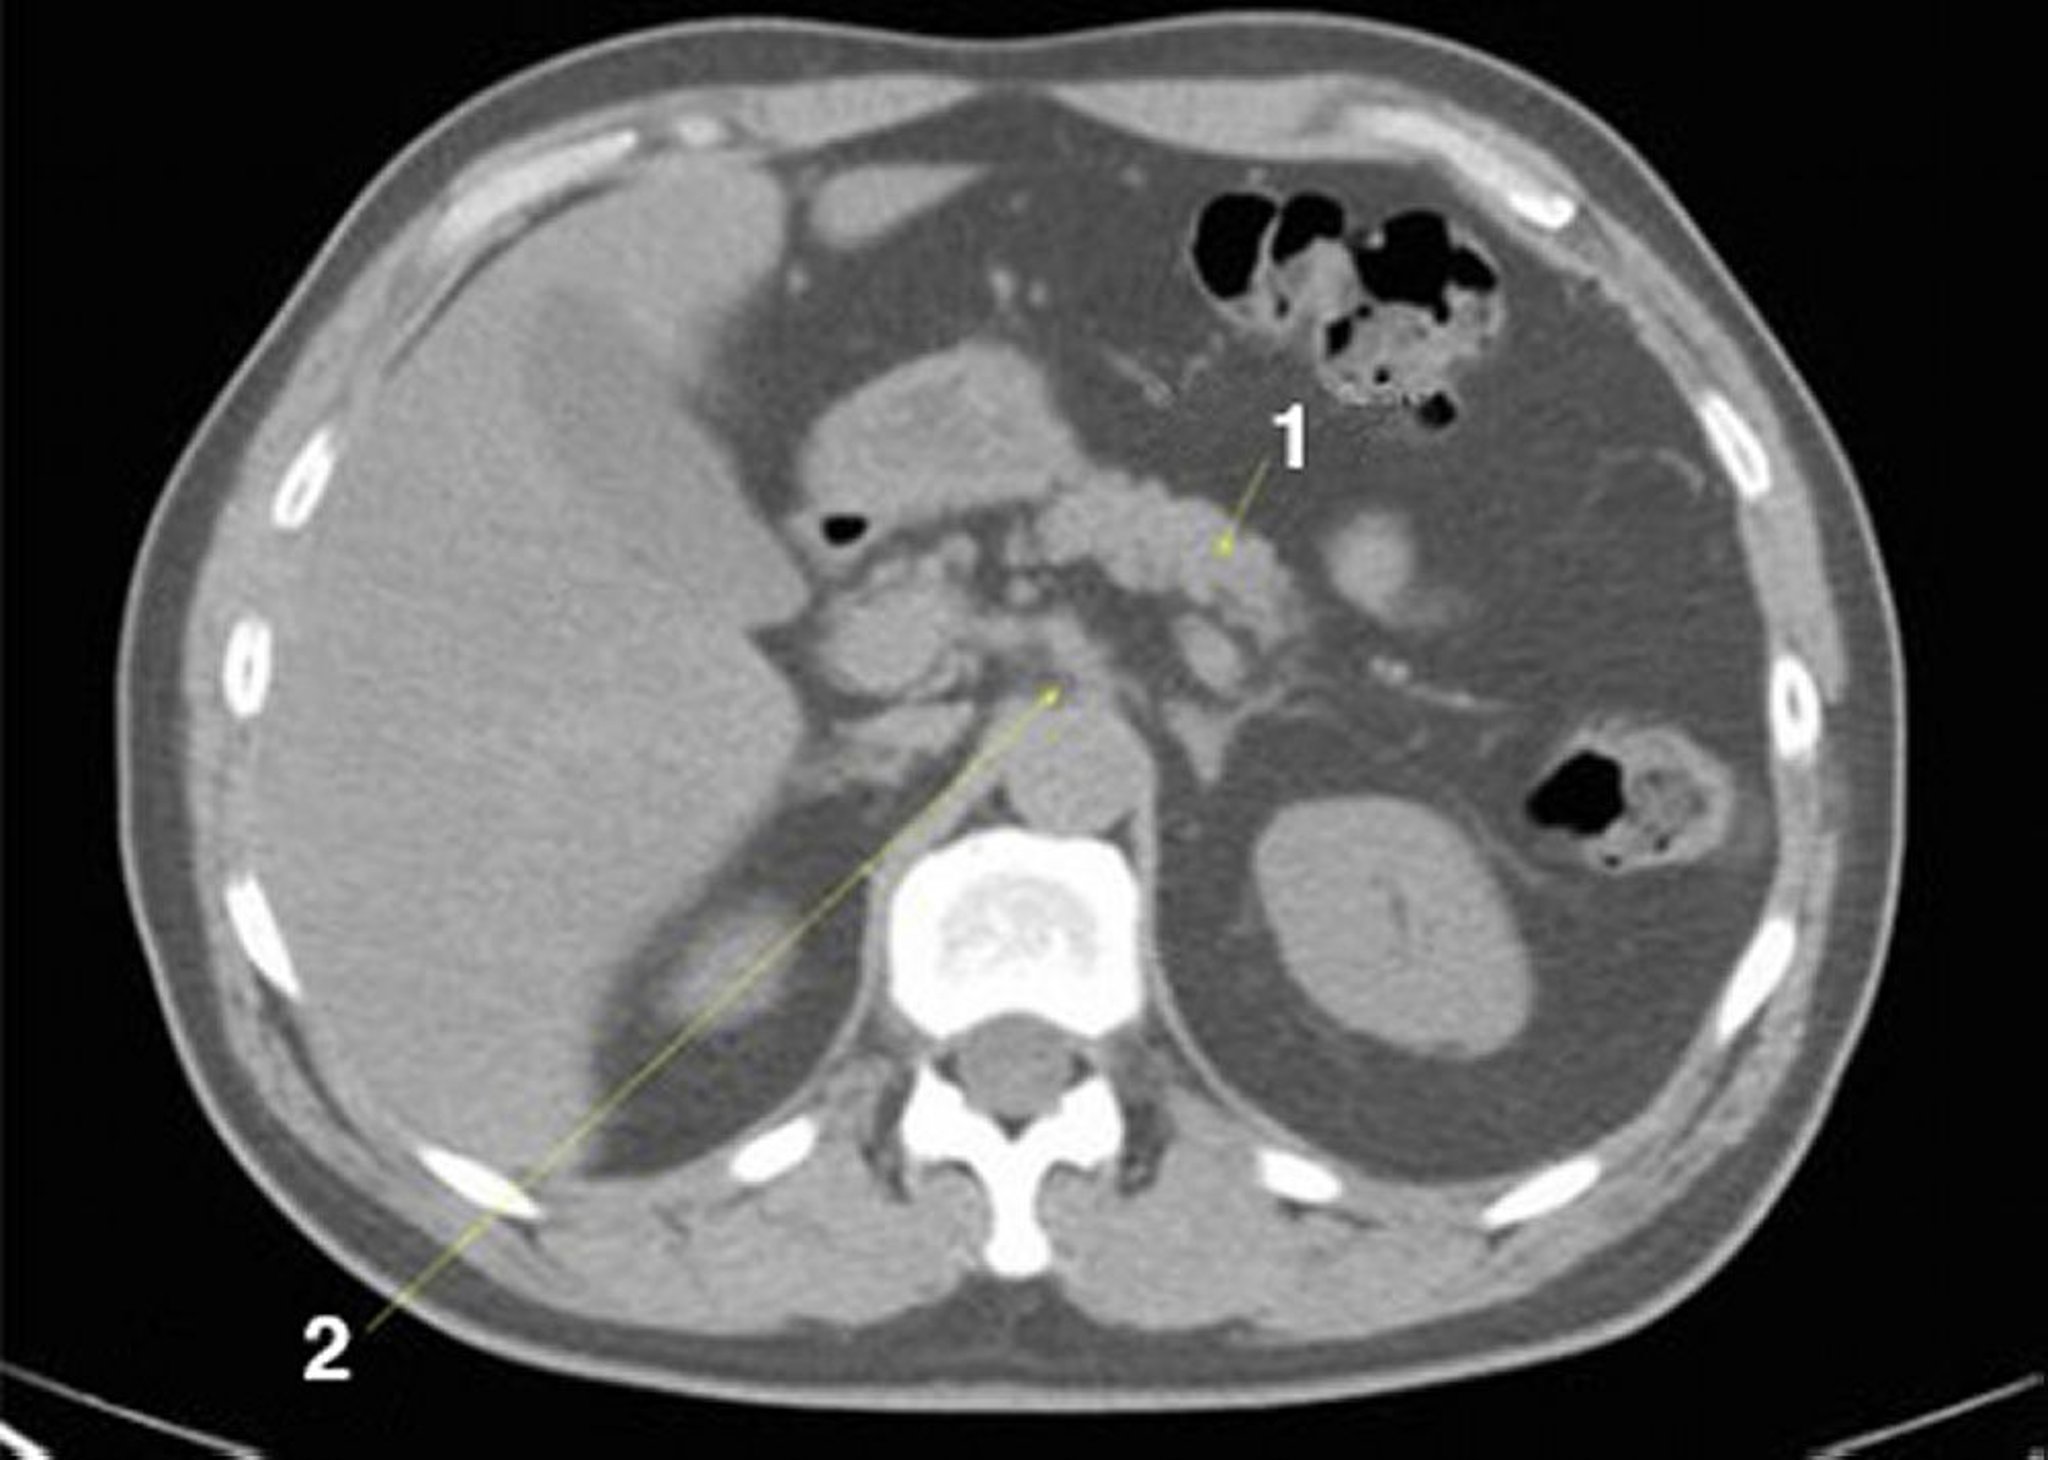

TDM sans contraste de l'abdomen et du bassin montrant une anatomie normale (diapositive 9)

1 = pancréas; 2 = axe cœliaque.